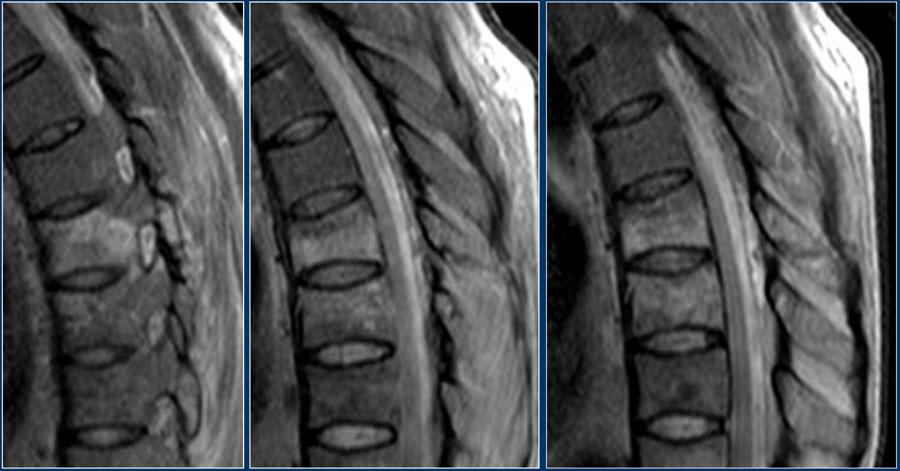

Tuy nhiên, CT cho thấy một đường gãy mảnh qua mặt trước thân đốt sống và cả qua mỏm gai.

Tiếp tục xem các hình ảnh MRI.

Do tính toàn vẹn của PLC phụ thuộc chủ yếu vào các cấu trúc dây chằng, đôi khi cần chụp MRI để chẩn đoán đầy đủ bệnh lý PLC, đặc biệt khi không có trật khớp hoặc đứt đoạn trên CT.

Đặc điểm trên MRI của bệnh lý PLC bao gồm:

- Xác định: 3 điểm

- Mất tín hiệu thấp bình thường của dây chằng vàng hoặc dây chằng gai trên trên chuỗi xung T1W và T2W.

-

Không xác định:

2 điểm - Phù nề không có đứt rõ ràng; tăng tín hiệu của dây chằng gai liên đốt hoặc dọc theo các khớp mỏm khớp trên T2 SPIR hoặc STIR.

MRI có xu hướng chẩn đoán quá mức tổn thương PLC (4).